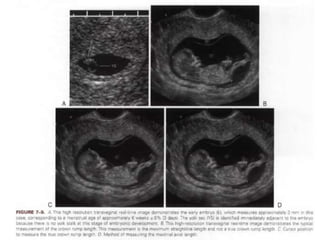

EMBRYO

 At 51/2 weeks, when the CR length is 2.o mm,

embryonic disc is situated between the yolk

sac and amnion.

 As the resolution of the ultrasound

equipment improves, visualization of the

embryonic structures become possible.

2.CROWN – RUMP LENGTH

( up to 11 weeks)

 GA closely correlates with CR length from 6

weeks until the end of the first trimester.

 The CRL is the length of the embryo or fetus

from the top of its head to the bottom of its

torso.

 It is measured as the longest dimension of

the embryo, excluding the yolk sac and

extremities.